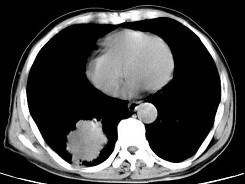

问题 男,66岁,胸痛一月,胸部CT如图,最可能的诊断是 ( )

选项 A、右下肺错构瘤 B、右侧炎性假瘤 C、右下肺动静脉瘘 D、右下肺肉瘤 E、右下肺周围型肺癌

答案 E